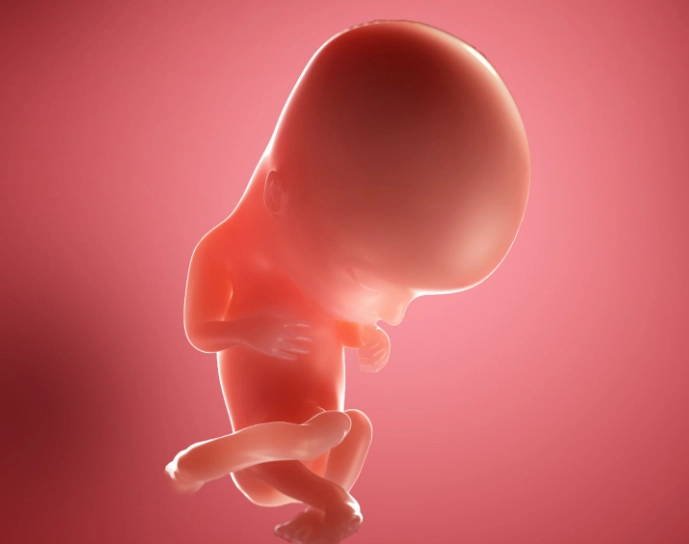

Your baby is no longer a tiny cluster of cells. By 12 weeks, they're about the size of a lime, measuring roughly 2.1 inches (5.4 cm) from crown to rump. The developments are staggering:

- Reflexes in Action: Fingers and toes have fully separated, and tiny nails are forming. The baby can make fist-clenching movements and may even suck its thumb.

- Organ Systems Go Live: The kidneys are starting to produce urine, which goes into the amniotic fluid. The bone marrow is beginning to make white blood cells.

- Facial Features Defined: The eyes, which started on the sides of the head, have moved closer together. The ears are nearly in their final position.

For you, the uterus has grown enough to start rising out of the pelvic cavity. This often means less pressure on your bladder (goodbye, constant bathroom trips for a little while) and sometimes the beginning of a subtle bump, especially if it's not your first pregnancy.